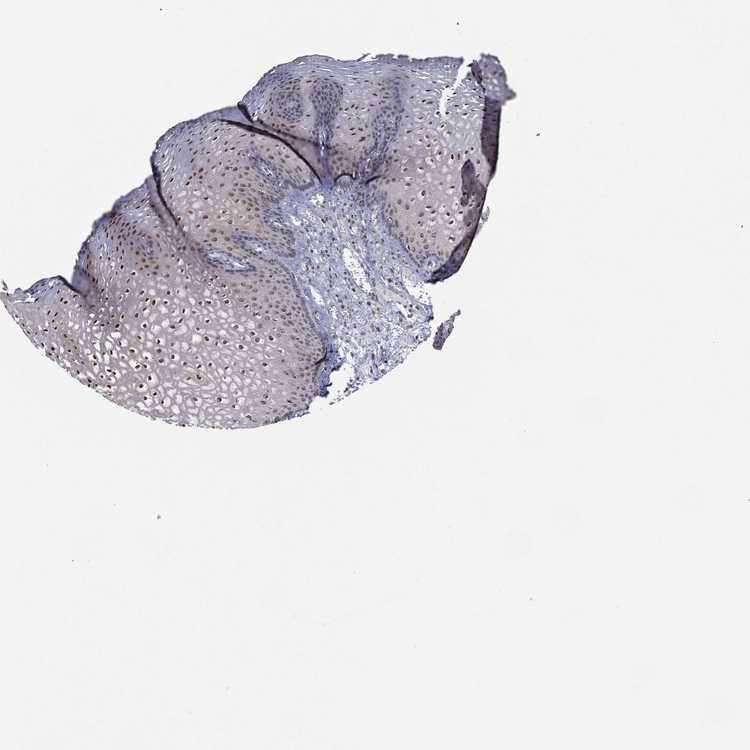

ESOPHAGUS - Antibody stainingi

Antibody staining in the annotated cell types in the current human tissue is reported as not detected, low, medium, or high, based on conventional immunohistochemistry profiling in selected tissues. This score is based on the combination of the staining intensity and fraction of stained cells.

Each image is clickable and will lead to virtual microscopy that enables deeper exploration of all samples and also displays staining intensity scores, fraction scores and subcellular localization as well as patient and tissue information for each sample.

Antibody HPA028539Antibody HPA061094

Squamous epithelial cells MediumHigh